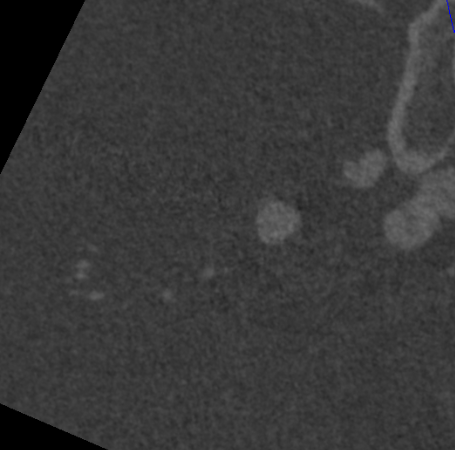

右侧颈总造影:右侧大脑中动脉瘤

右侧椎动脉硬膜外V2、V3段梭形扩张,前向血流通畅。